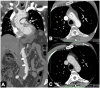

Non-traumatic thoracic aorta emergencies are associated with significant morbidity and mortality. Diseases of the intimomedial layers (aortic dissection and variants) have been grouped under the common term of acute aortic syndrome because they are life-threatening conditions clinically indistinguishable on presentation. Patients with aortic dissection may present with a wide variety of symptoms secondary to the pattern of dissection and end organ malperfusion. Other conditions may be seen in patients with acute symptoms, including ruptured and unstable thoracic aortic aneurysm, iatrogenic or infective pseudoaneurysms, aortic fistula, acute aortic thrombus/occlusive disease, and vasculitis. Imaging plays a pivotal role in the patient's management and care. In the emergency room, chest X-ray is the initial imaging test offering a screening evaluation for alternative common differential diagnoses and a preliminary assessment of the mediastinal dimensions. State-of-the-art multidetector computed tomography angiography (CTA) provides a widely available, rapid, replicable, noninvasive diagnostic imaging with sensitivity approaching 100%. It is an impressive tool in decision-making process with a deep impact on treatment including endovascular or open surgical or conservative treatment. Radiologists must be familiar with the spectrum of these entities to help triage patients appropriately and efficiently. Understanding the imaging findings and proper measurement techniques allow the radiologist to suggest the most appropriate next management step.